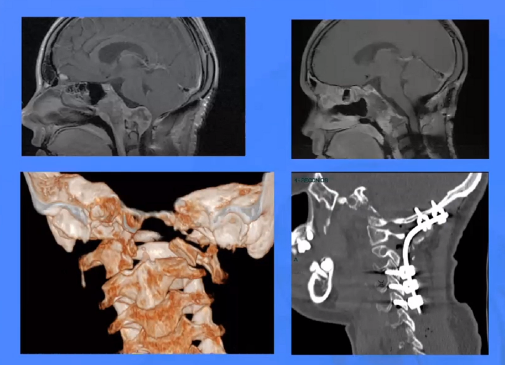

▼这是几年前做的一个手术,先把鼻中隔先推开,然后推开那些正常的组织,这里磨掉枕髁,暴露舌下神经管。虽然很具有挑战性,但是手术做得还是不错的,我们对病人进行了长期的随访,因为我们把全部的就是切开的软组织都复位了,所以看起来还可以,经过内固定以后,病人的颅颈交界区是很稳定的。

▼这个病例,它影响了颈1颈2,然后没有侵袭到硬膜内,我就不考虑用内镜了。考虑到脑脊液的释放等问题,这里我用了后外侧的一个入路。利用45度的内镜往上看,往上磨除岩骨的后方,可以一直暴露颈内动脉的岩骨段,然后海绵窦段。然后在显微镜下我们可以进行双手的操作,神经外科医生就比较熟悉的了。我们在做手术切除肿瘤切完了之后,还要进行固定。